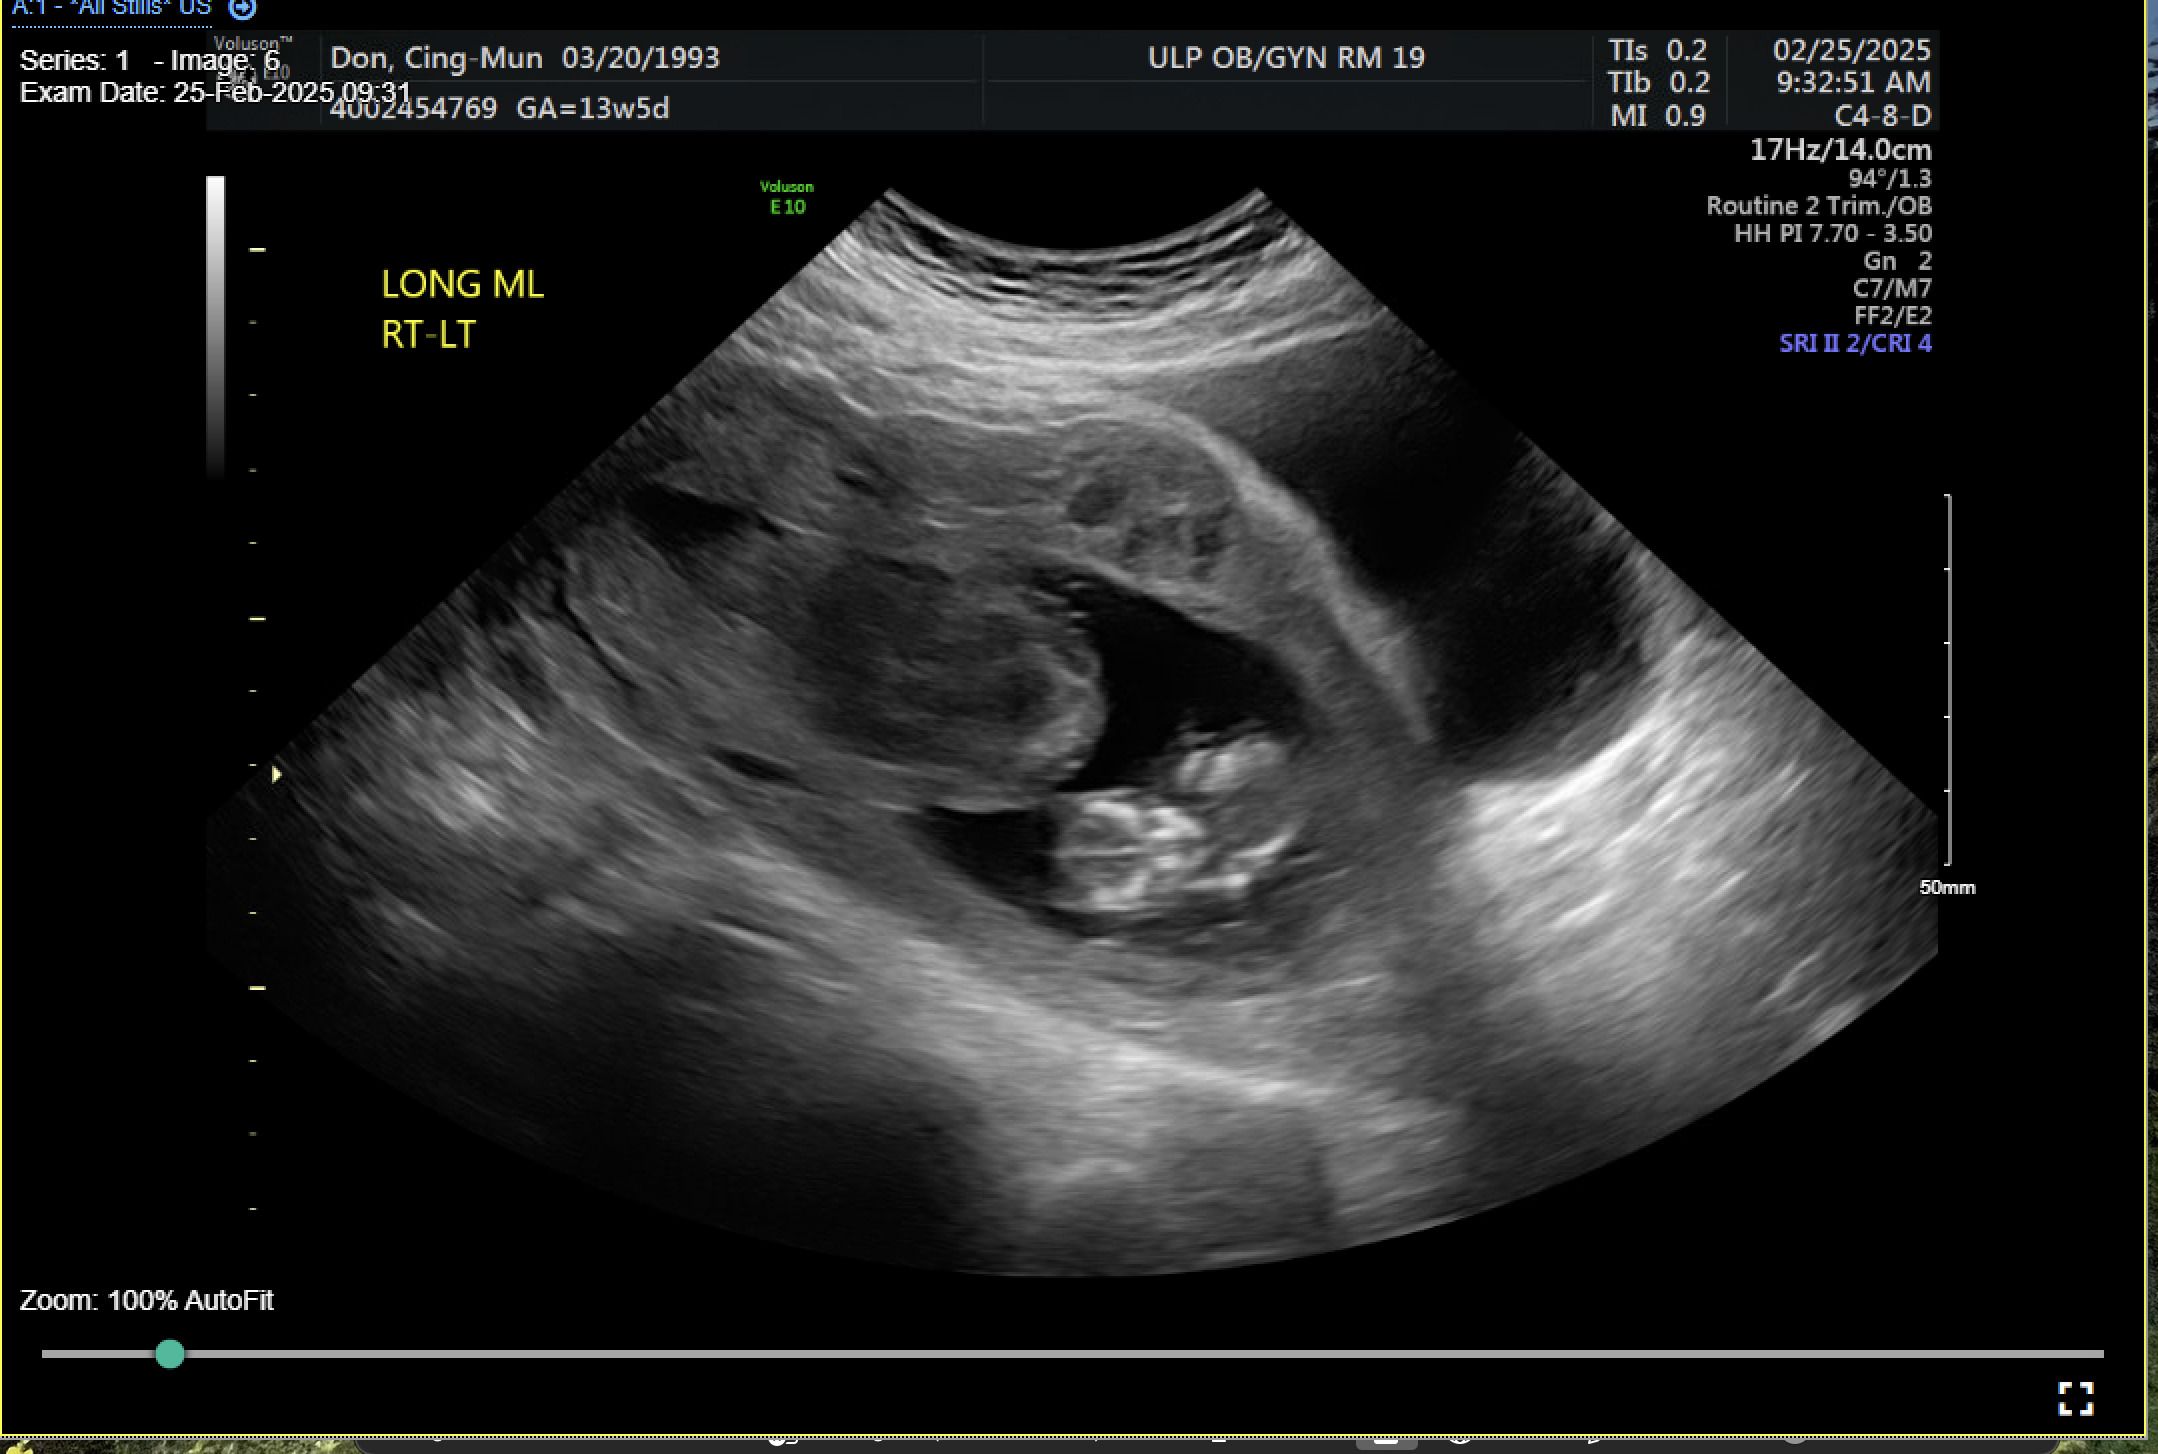

Results

A 31-year-old gravida 2 para 1001 at 13 weeks and 6 days gestation by a 7-week ultrasound presented to ULH for surgical management of a missed abortion in the setting of suspected CSP versus PAS. The patient had previously been seen at an outside hospital emergency room for concerns of bleeding and pelvic pain. Ultrasound workups for these concerns were significant for viable intrauterine pregnancy and moderate subchorionic hemorrhage superiorly, grossly measuring 5 cm at the largest dimension. Two weeks after her initial emergency department (ED) visit, the patient was seen in our practice’s general obstetric clinic. A first trimester ultrasound was performed at this time and again demonstrated a 5 cm subchorionic hemorrhage (Figure 1). At this time, concern for CSP versus PAS was also noted, and the patient was advised to return for a follow-up scan. When the patient returned for further evaluation of placental pathology, ultrasound revealed fetal demise with absent fetal cardiac activity (Figure 2). Following discussion with the maternal fetal medicine (MFM) provider, the patient ultimately elected for surgical evacuation of the products of conception to mitigate spontaneous bleeding risks in the setting of CSP versus PAS.